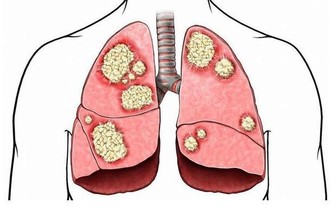

再比如多數的抗腫瘤藥。西藥因藥物結構明確,相比中藥,肝損傷較為明確!